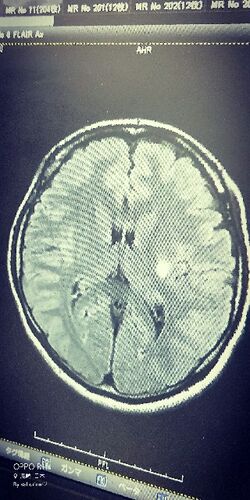

ただいま。 1日がかり。 即入院でもおかしくないんだってさ。 脳梗塞(´・ω・`) やっぱりな。 どう考えても、そうやろな。。 もう、脳細胞は死にました。 はあ。 結構大きな白でしたわ。 色々整理せなあかんな。 このブログもやめるかもしれません。 お金かか…